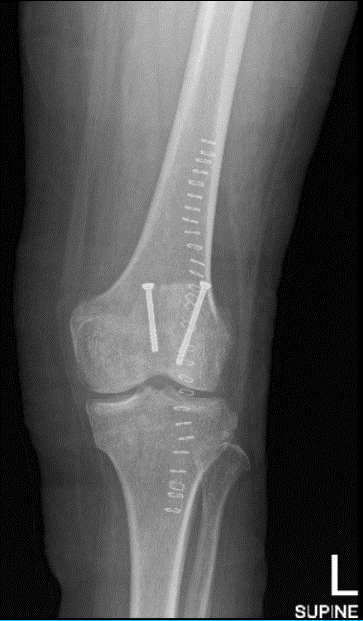

Case Study: Left Patellar Fracture Revision, Open Reduction and Internal Fixation with Tension Band in a 68 year-old patient

A 68 year-old patient was in our office with complaints post op x-rays on follow up showed cut through of the screws and failure of fixation with displacement of fracture. Dr. Karkare discussed treatment options and the patient opted for surgical management in the form of revision.

When the fracture was reduced well, it was then decided to try a tension band wiring. Two guidewires were passed medially and laterally and conversion. Findings in an acceptable position in AP and lateral view and deep enough.

Drilling was done over the guidewires and 4-mm cannulated cancellous screws were put. Both the 4-mm screws were undersized by 6 mm from measuring the guidewires. A 2-mm FiberTape was passed through these guidewires in a figure-of-eight configuration. This FiberTape showed good reduction so that the FiberWire was tied with a knot on the superolateral aspect.

The fixation was augmented with the use of 2-mm FiberTape x2 in the form of cerclage around the patella. Final fixation was achieved well. The knots were tied and buried into the tissue. The knee was thoroughly irrigated and drained.

The patient was seen for a follow up visit and presented X-ray result that showed postsurgical changes over the patella with satisfactory position of the hardware. Otherwise, unremarkable examination.

Left knee X-ray AP and Lateral